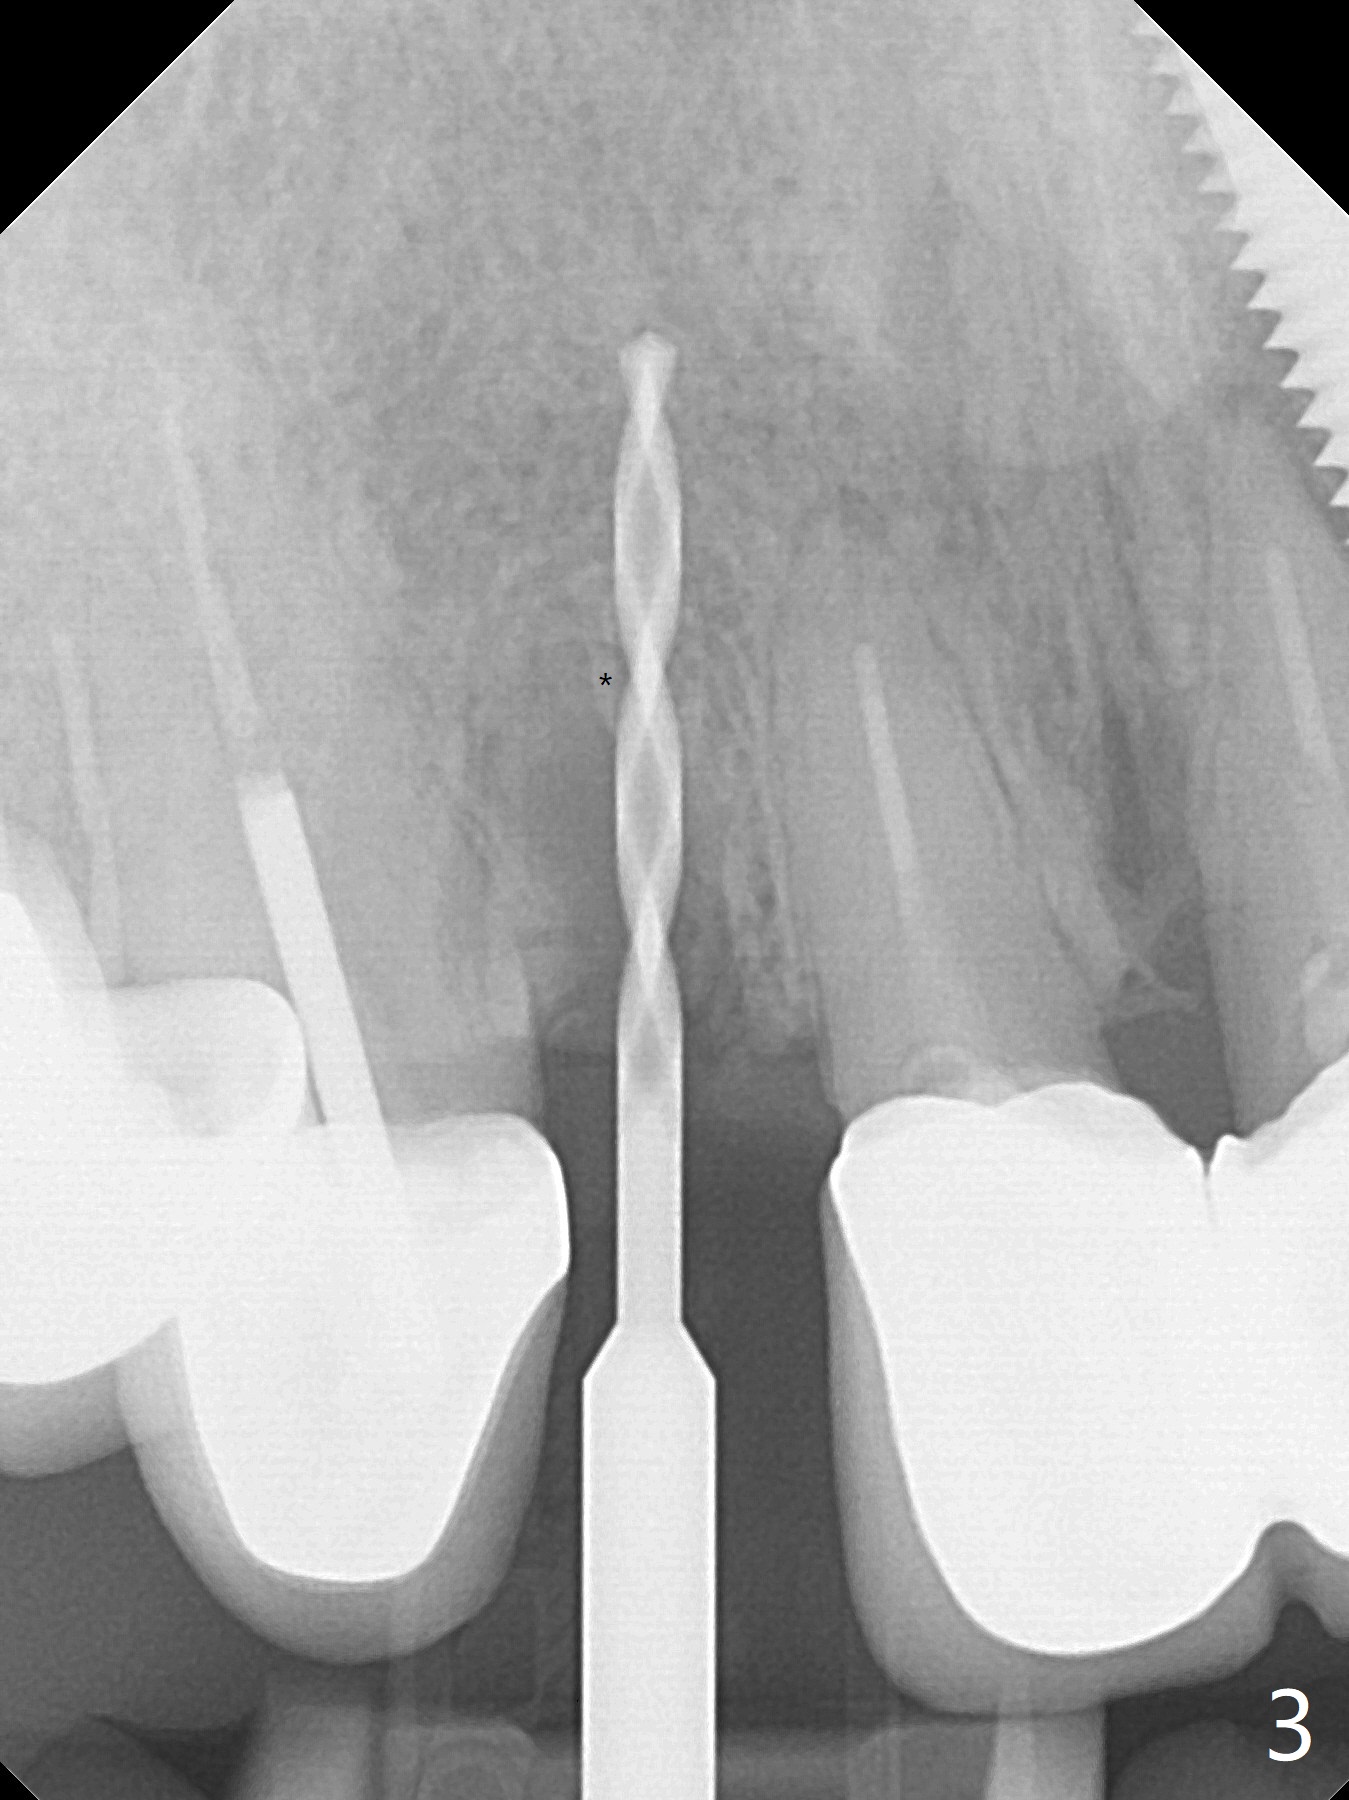

The edentulous area at #7 is narrow both buccopalatally and mesiodistally, whereas the crowns of the neighboring teeth are long (Fig.1,2). For the latter reason, it is difficult to remove the apical portion of the root, including gutta percha with surgical handpiece (Fig.3 *) for socket shield (Fig.2 *). To avoid the perspective implant touching socket shield, initial osteotomy is palatal. When a 2 mm drill is being used, the coronal end of the palatal plate starts to perforate. A 2.5x14 mm 1-piece implant is placed with 30 Ncm (Fig.4). The palatal plate is thin (Fig.5). Preop CT will help determine the position of initial osteotomy. The buccal gingiva seems to have been re-attached to the underlying alveolus and the provisional 1 month postop (Fig.6). The teeth #8 and 9 fracture (an implant is placed at #8 and bone graft at #9, while the implant at #7 is osteointegrating (Fig.7). In fact the shield is exposed without symptom. A year postop, another dental provider sends a photo of apparently hemorrhagic gingiva around #7 crown (Fig.8). A few days later with oral hygiene instruction, the gingiva around the exposed root piece is healthy (Fig.9). The root surface is reduced; with socket shield, there is no buccal plate collapse; in contrast the neighboring buccal plate (at #8 and 9) is concave (Fig.10). There is minimal exposure 11 days postop (Fig.11). The gingiva palatal to the shield is erythematous, a possible sign of periimplantitis. The socket shield at #7 appears to be fused with the buccal plate 11 months postop (Fig.12), as compared to the implant at #10 nearly 4 years postop (Fig.14). The buccopalatal widths at #7 and 10 are equivalent (Fig.13,15).